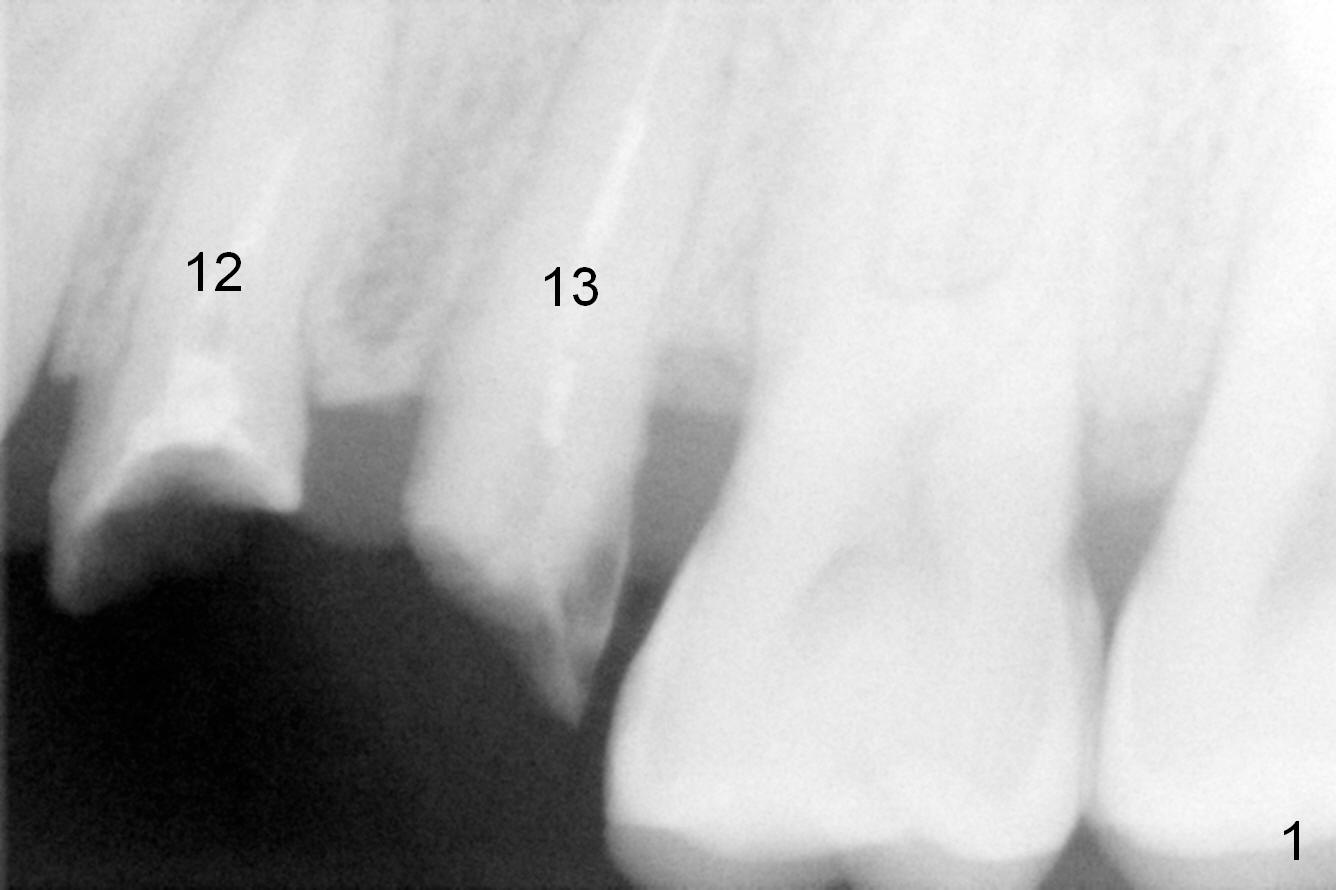

Taking 2 additional PAs with sensor 1 is frustrating (Fig.1,2), no apices shown. Osteotomy is done smoothly with 2 mm pilot drill at 20 mm, 2.5 mm reamer at 17 mm, and 3 mm reamer at 14 mm and 4.5x20 mm tap at 17 mm. The 1st intraop PA is taken with sensor 1 when 2 of 4.5x20 mm implants are placed (Fig.3); the implant at #12 is close to the root of the tooth #11. The 2nd PA is taken with sensor 2: the apex of #11 touches the implant at #12 (Fig.4). There is no separation when panoramic X-ray is taken (Fig.5). Effort is exerted to re-direct the osteotomy twice (Fig.6: tap; Fig.7: implant) without success. When the implant is removed, a PA is taken; it appears that the root of the tooth #11 has no damage (Fig.8). To obtain the best recovery, socket preservation is carried out with 50/50 cortical/cancellous allograft mixed with Osteogen (Fig.12 *) and Collagen Dressing (Fig.9: #12). A 2 (or 3)-unit provisional bridge (Fig.10: #12,13) is fabricated over the implant (Fig.9 I)/abutment (A) to cover these 2 sockets. After acid etching #11 D surface (Fig.9 >) and relining (Fig.11 *), the provisional bridge is bonded to the tooth #11 (Fig.11,12 black >) so that bone graft will be less likely dislodged.